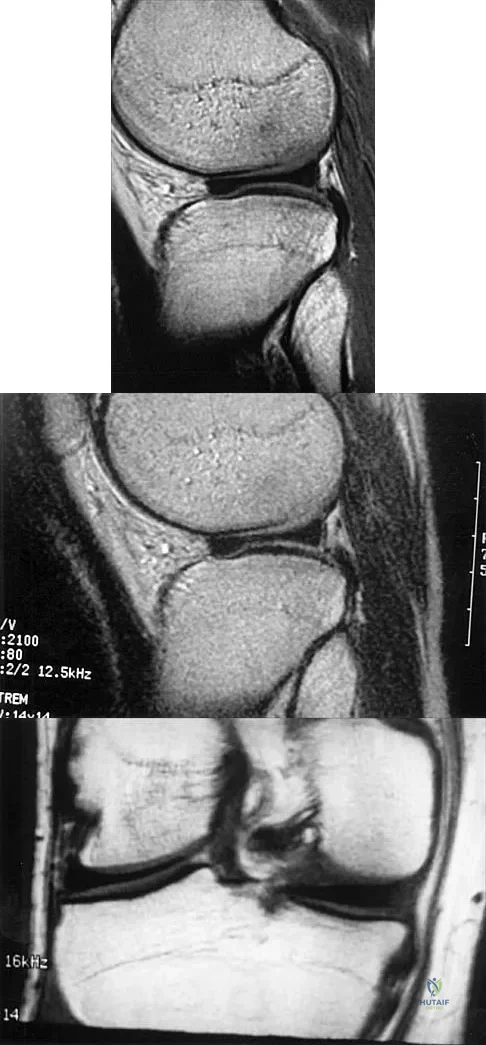

Question 38

A 26-year-old man has recurrent right knee pain. Figures 9a and 9b show consecutive sagittal T2-weighted MRI scans, and Figure 9c shows a coronal T1-weighted MRI scan. What is the most likely diagnosis?

Explanation